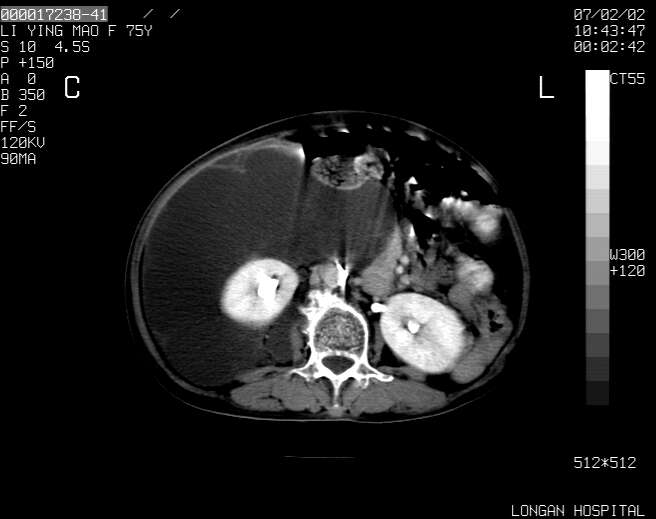

以下是引用dyqct在2007-2-10 8:53:00的发言:[br]考虑:1、肝脏多发囊肿[br] 2、左肾囊肿,右肾多发结石并积水。[br] 3、右胸少量积液。[br] 4、右肾周包裹性积液或淋巴管瘤(有见缝就钻的征象、薄隔、小结节状钙化)?[br] 5、腰椎动脉瘤样骨囊肿?[br] [br] [br]